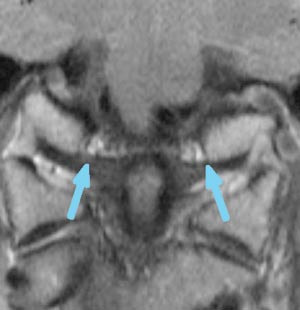

I den senere tid har mye av oppmerksomheten vært rettet mot bildediagnostisk fremstilling av strukturelle forandringer i kraniocervikalovergangen og kirurgisk behandling av antatt instabilitet i dette området. Hypotesen om en strukturell skade forårsaket av nakkeslengskade har vært gjenstand for forskning i flere år, men i en rapport fra Senter for medisinsk metodeutvikling i 2000 (3) var hovedkonklusjonen at det på det tidspunkt ikke var signifikante funn ved MR-undersøkelse av nakken ved nakkeslengskade. Etter dette tidspunkt har det imidlertid vært en betydelig utvikling innen MR-teknologi, og i nyere studier har man rettet oppmerksomheten mot støttestrukturer (leddbånd, leddkapsler og bindehinner) i overgangen mellom hodet og de to øverste nakkevirvlene. I disse arbeidene har man lagt vekt på anatomisk detaljfremstilling av ulike strukturer. De viktigste strukturene som er undersøkt med disse nye metodene er alarligamentene. Disse leddbåndene strekker seg fra toppen av C2 (dens axis) til skallebeinet. Alarligamentenes funksjon er å begrense rotasjon og sidebøyning av hodet (fig 1, 2).

De mest betydningsfulle studiene på dette feltet er utført av nevroradiologen Jostein Kråkenes og medarbeidere ved Haukeland Universitetssjukehus. De har undersøkt 92 pasienter med kronisk nakkeslengsyndrom og 30 friske frivillige. Pasientene ble undersøkt 2 – 9 år etter ulykken. I fire arbeider er det beskrevet utvikling av MR-metoden, bildefunn i alarligamenter, transversal ligamentet og andre støttestrukturer (8) – (11). De har foreslått et graderingssystem 0 – 3 basert på hvor omfattende signalforandringene i de ulike strukturene har vært. Et hovedfunn i disse studiene er at det er påvist betydelig flere forandringer i de ulike støttestrukturene hos pasienter med nakkeslengskade enn hos kontrollgruppen. I alarligamentene ble det påvist signalforandringer grad 2 og grad 3 (de mest uttalte signalforandringene) hos 45 pasienter, mens tilsvarende signalforandringer ikke ble funnet i kontrollgruppen.